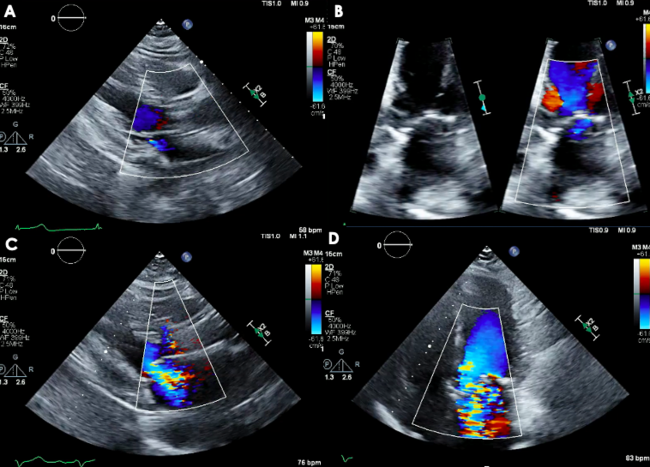

An 83-year-old woman with symptomatic severe aortic stenosis (AS) was referred for transcatheter aortic valve replacement (TAVR). Diagnostic left heart catheterization (LHC) documented diffuse 3-vessel coronary artery disease (CAD) (Videos 1-3). Transthoracic echocardiogram (TTE) showed normal biventricular function, severe AS, and minimal mitral regurgitation (MR) (Figure 1A and B; Video 4). The Heart Team deemed that she was at high/prohibitive surgical risk given multiple comorbidities and frailty.

The patient underwent transfemoral TAVR with a 25-mm Navitor valve (Abbott) after initial ballon aortic valvuloplasty (BAV). TTE and angiography documented normal valve positioning and function, and normal coronary perfusion. Within a few minutes of the deployment of the valve, the patient developed persistent hypotension and vasopressors were initiated. TTE showed anteroseptal hypokinesis and severe MR with a centrally directed jet (Figure 1C and D; Video 5). The patient was intubated, and transesophageal echocardiogram (TEE) confirmed severe MR with a broad, centrally directed jet from poor mitral leaflet coaptation (Figure 2A and B; Videos 6 and 7). A diagnostic left heart cardiac catheterization showed no changes in the underlying CAD. An intra-aortic balloon pump was placed, and TEE showed MR improvement from severe to mild (Figure 2C; Video 8). The patient was moved to the cardiac intensive care unit for continuous hemodynamic monitoring. Her clinical course progressively improved and she was discharged home on post-procedure day 7 in stable condition.